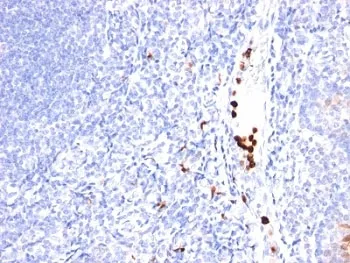

CSF3 Antibody / Granulocyte-Colony Stimulating Factor

CSF3 Antibody / Granulocyte-Colony Stimulating Factor

- Description: This mAb recognizes granulocyte-colony stimulating factor (G-CSF) in the cytoplasm of mature granulocytes. It shows no reactivity with any other cell types. Markers of myeloid cells are useful in the identification of different levels of cellular differentiation. It reacts with early precursor and mature forms of myeloid cells. It is useful for the detection of myeloid leukemias and granulocytic sarcomas. It can be used as a marker of granulocytes in normal tissues or inflammatory processes.G-CSF is a pleiotropic cytokine that influences differentiation, proliferation and activation of the neutrophilic granulocyte lineage. The human G-CSF cDNA encodes a 207 amino acid precursor containing a 29 amino acid signal peptide that is proteolytically cleaved to form a 178 amino acid residue mature protein. Two G-CSFs, which are identical except for a three amino acid deletion in the amino-terminus of one form of the protein have been isolated from human cells. Murine and human G-CSF s share 73% sequence identity at the amino acid level.

- Applications: IHC-P